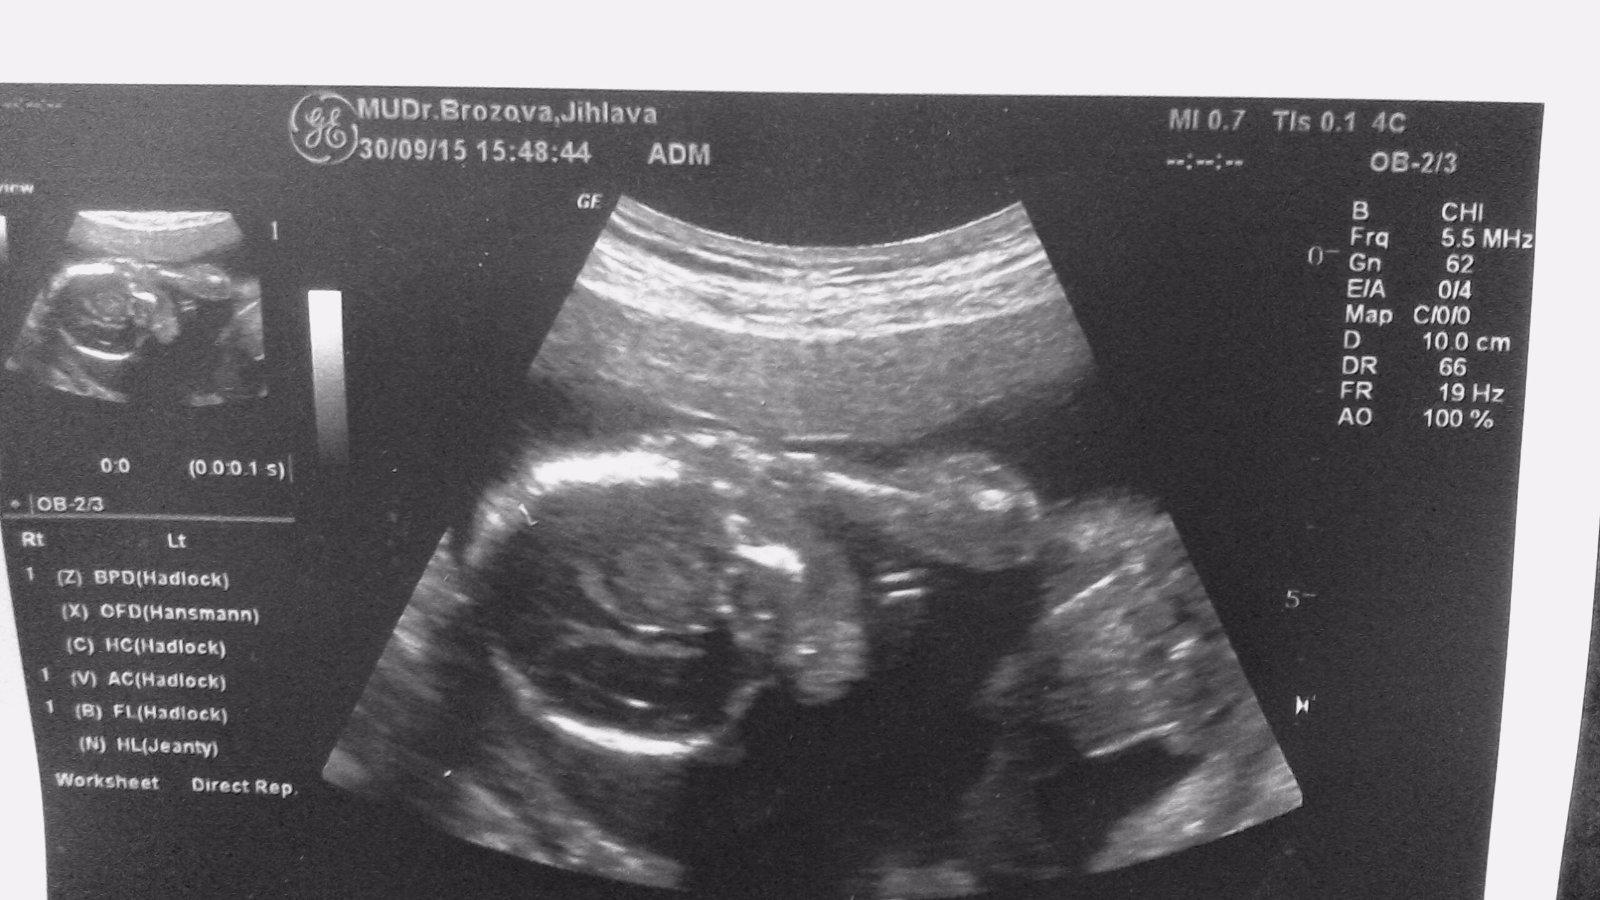

Je to holčička nebo chlapeček? Foto ultrazvuku

@satynka Mně je pohlaví jedno 🙂. No ale jak jsem doma koukala na tu fotku, tak se mi taky zdá že to je kluk. Leda že by to byl kousek bříška, ale to se mi nezdá tak symetrické ( vyznačím to )...

Tak ještě jak to vidím já 🙂, třeba to i pomůže někomu se lépe orientovat ve vlastních fotkách 😉